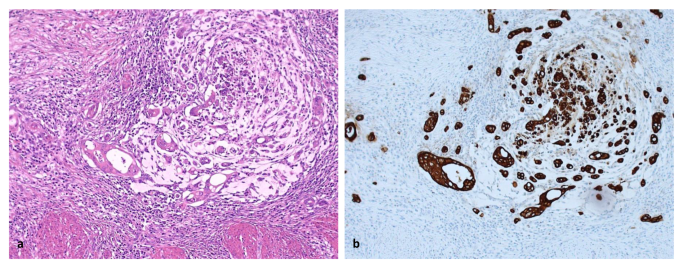

H&E stained tissue sections from the primary tumor of 4 μm thickness are analyzed by conventional microscopy. Areas appearing to have the highest amount of stroma are selected using the × 2.5 or the × 5 lens. Hereafter, an area where both tumor and stromal tissue are present within this vision-site is selected using a × 10 objective. Tumor cells are to be present at all borders of the selected image field (Fig. 1). The amount of stroma tissue is estimated per 10% increment (10, 20, 30%, etc.) per image field. For statistical analysis, stromal ratio groups are divided in stroma-high and stroma-low groups. Stroma-high is defined as > 50% stromal area, and stroma-low as ≤ 50% stromal area in the histological section, as determined a priori to have maximum discriminative power [4]. Even if there is only one image field with a stroma-high score, this image field is decisive.

Fig. 1

figure 1

Examples of a stroma-low (a) and stroma-high (b) colon carcinoma, which meet the criteria for the presence of vital tumor cells on all four sides of the field of vision (arrows) and are thus correct for scoring. When tumor cells are only present at two (c) or three (d) sides of the field of vision (mucus is not included in estimating TSR), these areas are not suitable for scoring (Images displaying the microscopic view, all images × 100 magnification)